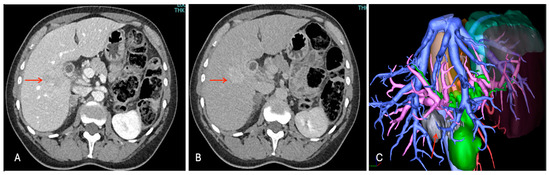

3.2.1. Case 1

3.2.2. Case 2